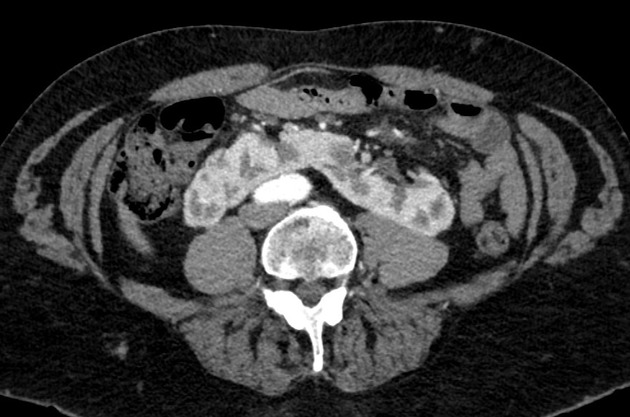

✅الـ Horseshoe Kidney هو تشوه خلقي يصيب الكلى، و فكرته ببساطة إن الجنين وهو لسا في بطن أمه وعمره بضع أسابيع، الكليتين بدل ما تصعد كل وحدة لمكانها الصحيح على اليمين واليسار، يلتصق طرفهم السفلي (Lower Poles) ببعض وتتحد وتكون شكل حدوة الحصان (U-Shape) وهذا هو اللي خلاهم يسمونها بهالاسم، والكلية الملتحمة هذي تبقى اوطى من مكانها الطبيعي لأن شي اسمه الـ Inferior Mesenteric Artery يوقف صعودها ويمنعها من إنها تكمل رحلتها لفوق، والنتيجة إن الكلية تتعلق في منتصف البطن قدام العمود الفقري.

الحين وش اللي يصير للمريض؟ كثير من الناس ما يحسون بأي شي وتُكتشف الكلية بالصدفة في أشعة، لكن المشكلة الرئيسية إن الـ Ureter اللي هو الأنبوب الناقل للبول يطلع من مكان غلط ويصير عنده انحناء أو انضغاط، وهذا يسبب ركود البول (Urinary Stasis) وبالتالي يرفع خطر تكون حصى الكلى (Nephrolithiasis) والتهابات المسالك البولية المتكررة (Recurrent UTIs) وحالة خطيرة اسمها Hydronephrosis وهي إن البول يتراكم ويضغط على الكلية ويورمها، وكمان المريض يكون أكثر عرضة لنوع من أورام الكلى اسمه Wilms Tumor خصوصاً عند الأطفال، والتشخيص يكون بالـ Ultrasound أو الـ CT Scan اللي يظهر فيه الشكل المميز لحدوة الحصان بوضوح.

احمد@AB_drmd

🚨🚨🚨ايش الpathology الموجوده في الاشعة؟